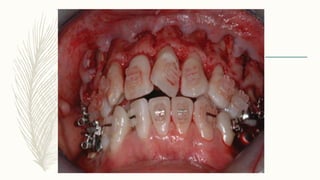

CASE REPORT (Journal ofInterdisciplinary Dentistry / Sep-Dec 2012 / Vol-2 / Issue-3) – A 38-year-old female patient had a complaint of forwardly placed upper and lower front teeth with spacing between the teeth – DIAGNOSIS - Angles Class I malocclusion with proclination and spacing of upper and lower anterior teeth – The patient consented to the PAOO – Prior to surgical and orthodontic treatment, periodontal health of the patient was restored by phase I periodontal therapy including plaque control measures and scaling and root planing.